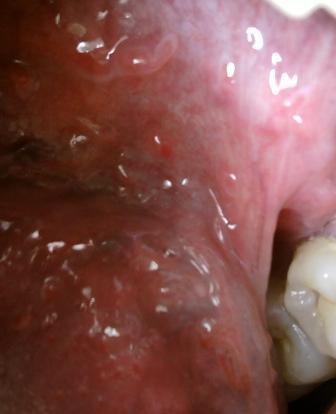

石家庄治疗尖锐湿疣专科医院的费用但是具体的治疗费用是受到多种因素的制约和影响的,但是并不是天文数字,大家应该了解这一点,不要因为任何原因而耽误治疗。不管是什么疾病,只有针对病因进行治疗,才可以达到很好的治愈的目的。尖锐湿疣在积极去除湿疣体的同时,也应该注重体内病毒的清楚,只有这样才可以快速治愈疾病,长期得不到及时的治疗,就会对人体健康带来严重的危害,危害大不大尖锐湿疣不及时治疗,湿疣体就会逐渐加重,给日后的治疗带来很大的难度,同时还会诱发各种炎症。

石家庄治疗尖锐湿疣专科医院的费用治疗尖锐湿疣的方法还是比较多的,主要有以下几种:冷冻治疗尖锐湿疣、激光治疗尖锐湿疣、微波治疗尖锐湿疣、电烧治疗尖锐湿疣、手术治疗尖锐湿疣等。以上就是石家庄九洲皮肤病医院专家的观点,希望可以帮助到您,如有任何不理解的情随时拨打石家庄性病医院九洲康复热线:66560637这里有专家24小时为您答疑解惑。